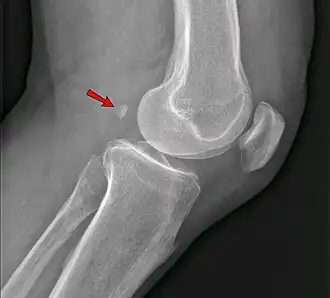

Knee

• The fabella is present in 10% to 30% of individuals.[1]